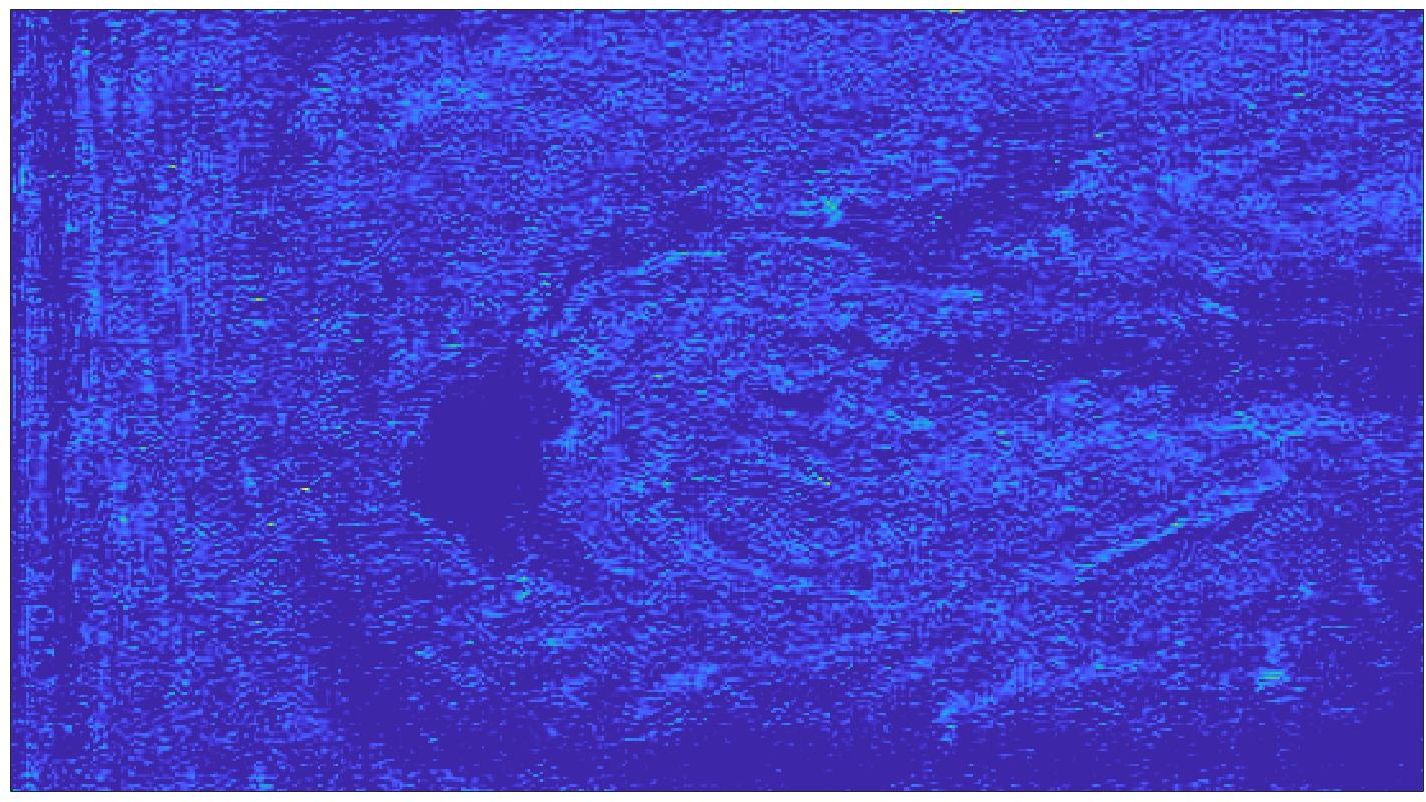

Our framework visually improves the results, in terms of blurring and artefacts. This result is more evident in the magnification of the ear of the foetus (Fig. 3), the mitral valve (Fig. 4), and the mass edges (Fig. 5). Fig. 6 shows the error image of the three anatomical districts with both 2X and 4X up-sampling factors, with the maximum error in the scale . The error is more evident in the contours of the anatomical structures; moreover, the abdominal district shows a smaller error than the cardiac and obstetric ones. We underline that the view for each image is scaled to its maximum, to improve the visualisation of the error.

The analysis of the absolute value of the difference between the input and the prediction of the network (Fig. 9) shows that the alteration of our prediction to the pixel values ranges from 0 to a maximum absolute value of 20, mainly located on the edges of the anatomical structures; furthermore, the black uniform areas are less affected by the prediction. In terms of the distance between the input and the prediction, we do not observe a significant difference among anatomical districts and between 2X and 4X up-sampling.